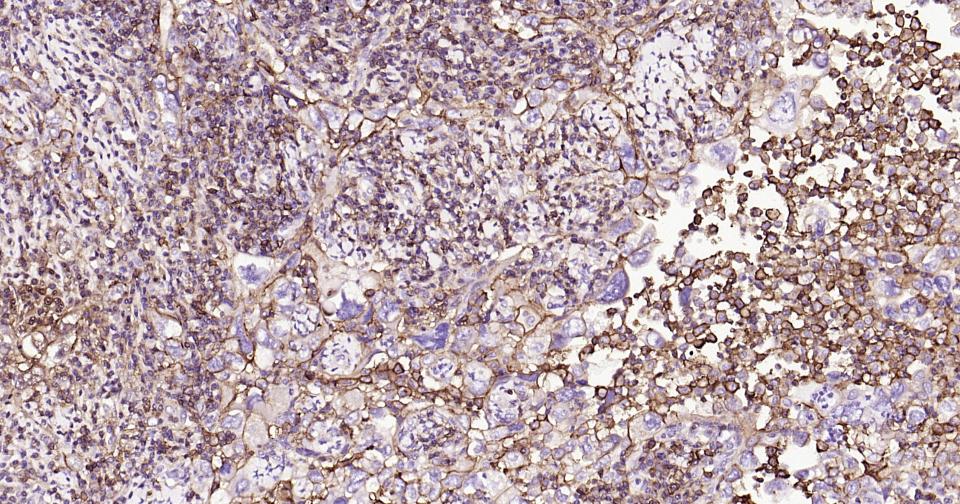

| 应用 | 已检合格种属 | 预测种属 | 推荐稀释比例 |

|---|---|---|---|

| IHC-P | Human | 1:100-500 | |

| IHC-F | Human | 1:100-500 | |

| IF | Human | 1:100-500 | |

| Flow-Cyt | Human | 1ug/Test | |

| ICC/IF | Human | 1:100-500 |